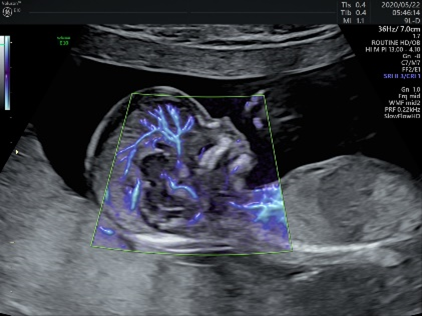

妊娠初期超音波検査は妊娠11週~13週の時期に行う、FMFのプロトコールに沿って詳細に行う超音波検査です。

- 心臓から出る大きな血管の流れに問題はないか

最近の超音波機器の性能はとても高くなってきており、小さな胎児でも超音波検査で、「大きな心臓の変化」「初期の中枢神経の変化」など、構造学的な異常が検出されるようになってきました。

これは胎児の首の後ろのむくみ(NT)の厚さを超音波検査で計測し、さらに妊婦さんの採血検査で得られる血清マーカーの値を計測し、それを母体年齢から計算される一般的な確率に組み合わせることで、妊娠している胎児固有のリスクを計算する方法です。